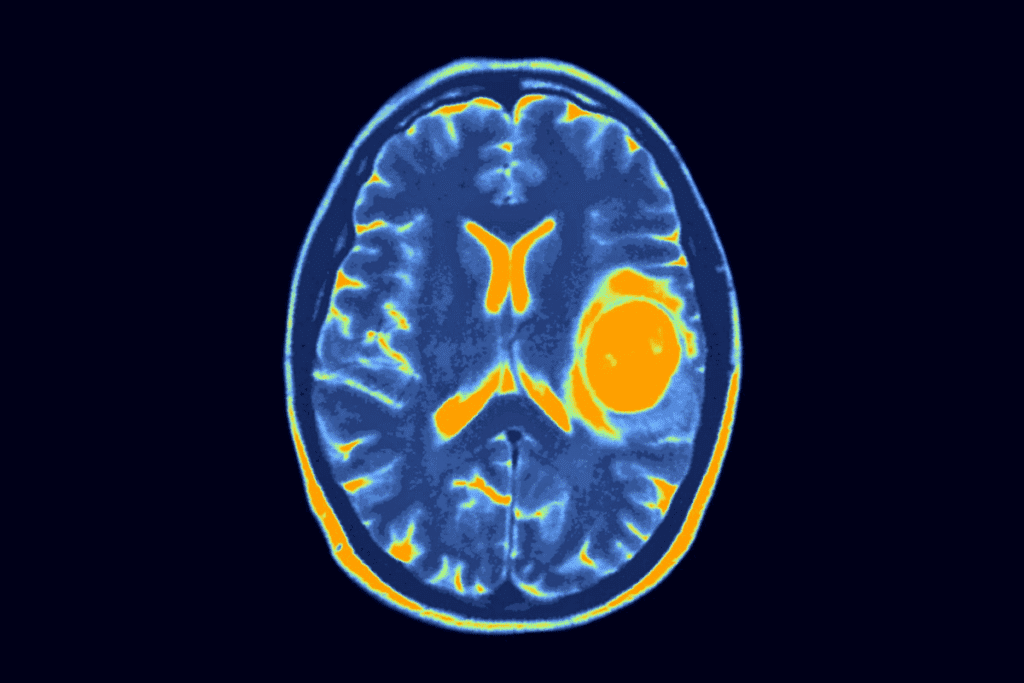

Advanced Imaging Modalities

For a detailed look at tumors, we use advanced imaging. Magnetic Resonance Imaging (MRI) is great for soft tissue tumors. It shows the tumor’s size and where it is. Computed Tomography (CT) scans help see tumors in the belly and chest. They give clear images for treatment planning.

Positron Emission Tomography (PET) scans check how active tumors are. They help tell if a tumor is cancerous and how well treatment is working.